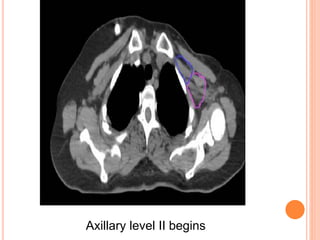

REGIONAL NODAL CONTOURING

SCF begins

Axillary level III begins

Axillary level II begins

Axillary level I begins

Axillary level I ends

IMC begins

IMC ends